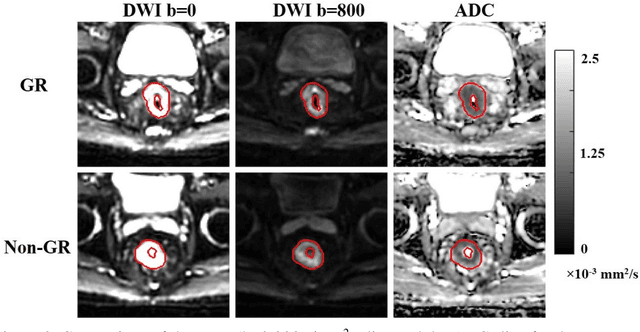

Abstract:Radiomic features achieve promising results in cancer diagnosis, treatment response prediction, and survival prediction. Our goal is to compare the handcrafted (explicitly designed) and deep learning (DL)-based radiomic features extracted from pre-treatment diffusion-weighted magnetic resonance images (DWIs) for predicting neoadjuvant chemoradiation treatment (nCRT) response in patients with locally advanced rectal cancer (LARC). 43 patients receiving nCRT were included. All patients underwent DWIs before nCRT and total mesorectal excision surgery 6-12 weeks after completion of nCRT. Gross tumor volume (GTV) contours were drawn by an experienced radiation oncologist on DWIs. The patient-cohort was split into the responder group (n=22) and the non-responder group (n=21) based on the post-nCRT response assessed by postoperative pathology, MRI or colonoscopy. Handcrafted and DL-based features were extracted from the apparent diffusion coefficient (ADC) map of the DWI using conventional computer-aided diagnosis methods and a pre-trained convolution neural network, respectively. Least absolute shrinkage and selection operator (LASSO)-logistic regression models were constructed using extracted features for predicting treatment response. The model performance was evaluated with repeated 20 times stratified 4-fold cross-validation using receiver operating characteristic (ROC) curves and compared using the corrected resampled t-test. The model built with handcrafted features achieved the mean area under the ROC curve (AUC) of 0.64, while the one built with DL-based features yielded the mean AUC of 0.73. The corrected resampled t-test on AUC showed P-value < 0.05. DL-based features extracted from pre-treatment DWIs achieved significantly better classification performance compared with handcrafted features for predicting nCRT response in patients with LARC.